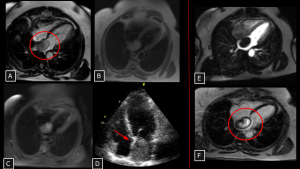

Fig 22: Case 23 – Cardiac Myxoma:

Cardiac MRI (A, B, C, E, F) reveals a lobulated mass in the left atrium. Note the high signal intensity on bright-blood sequences (circle in A) due to the mucinous/water-rich content, which can mimic a cyst. However, the lesion presents heterogeneous enhancement (circle in F), confirming it is a solid neoplasm and ruling out avascular thrombus. Echocardiogram (D) demonstrates the classic pedunculated attachment to the interatrial septum/fossa ovalis (arrow).

SYSTEMATIC APPROACH: 1. Age: Adults (30–60 years). | 2. Morphology: Lobulated, low-attenuation mass (mimics fluid). | 3. Enhancement: Heterogeneous (Solid). | 4. Relevant Anatomical Relationships: Left Atrium; attached to the Fossa Ovalis (Interatrial septum).